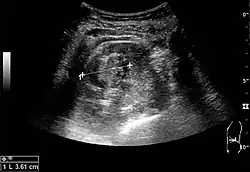

Renal ultrasonography

On renal ultrasonography, a solid renal mass appears in the US exam with internal echoes, without the well-defined, smooth walls seen in cysts, often with Doppler signal, and is frequently malignant or has a high malignant potential. The most common malignant renal parenchymal tumor is renal cell carcinoma (RCC), which accounts for 86% of the malignancies in the kidney. RCCs are typically isoechoic and peripherally located in the parenchyma, but can be both hypo- and hyper-echoic and are found centrally in medulla or sinus. The lesions can be multifocal and have cystic elements due to necrosis, calcifications and be multifocal (Figure 8 and Figure 9). RCC is associated with von Hippel–Lindau disease, and with tuberous sclerosis, and US has been recommended as a tool for assessment and follow-up of renal masses in these patients.[3]